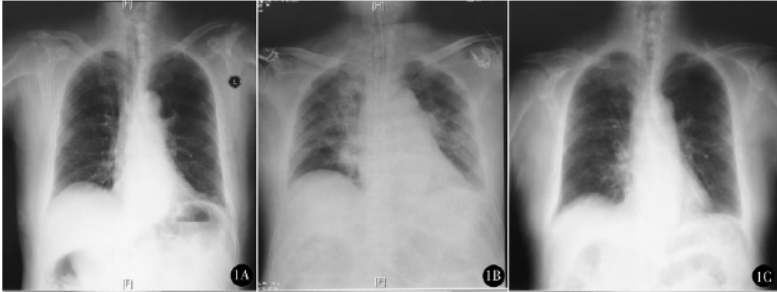

例2,女,77岁,身高153 cm,体重55kg。因“右侧腹股沟嵌顿疝”2015年6月25日急诊行腹股沟疝修补术。有高血压、冠心病、脑梗死,行颈动脉支架放置术后5个月,口服硫酸氢氯吡格雷75mg每日一次,未停药。胸片(图2A)、超声心动图等辅助检查未见明显异常。术前饱胃,禁饮2h。急诊入室,监测血压146/77mmHg,心率72次/min,SpO2 99%,面罩吸氧,静脉给予咪达唑仑2mg,在超声引导下行右侧腹横肌平面阻滞(transversus abdominis plane,TAP),麻醉用药为0.3%罗哌卡因30ml。

术中麻醉维持:1%~1.5%七氟烷,瑞芬太尼200μg/h,间断追加罗库溴铵10mg维持肌松。手术开始后即刻动脉血气分析pH值7.45,PaCO2 42mmHg,PaO2 172mmHg,SaO2 99%。手术过程顺利,手术时间190min,带气管导管入ICU。入ICU后血常规白细胞10.02×109/L,中性粒细胞百分比90.5%,动脉血气分析pH值7.48,PaCO2 34mmHg,PaO2 76mmHg。床旁胸片提示右下肺胸腔积液,右下肺炎症(图2B)。呼吸机辅助呼吸4天,SIMV+PSV模式,SpO2 98%~99%。静脉注射头孢哌酮舒巴坦(3g,8h一次)抗感染4天,抑酸、补液、营养治疗。术后第4天右下肺胸腔积液逐渐吸收,渗出改变较前好转(图2C),血常规正常,第5天拔除气管导管转回普通病房,第9天出院。随访6个月,未见相关并发症。

图2例2术前胸片(A)提示双肺纹理增多,右上肺见散在斑点状高密度影,右下肺见索条影;术后即刻胸片(B)提示双肺纹理增多,右肺可见斑片状密度增高影,右侧肋膈角模糊、浅钝;术后第4天胸片(C)提示右肺多发片状模糊影较前吸收,双侧肋膈角锐利